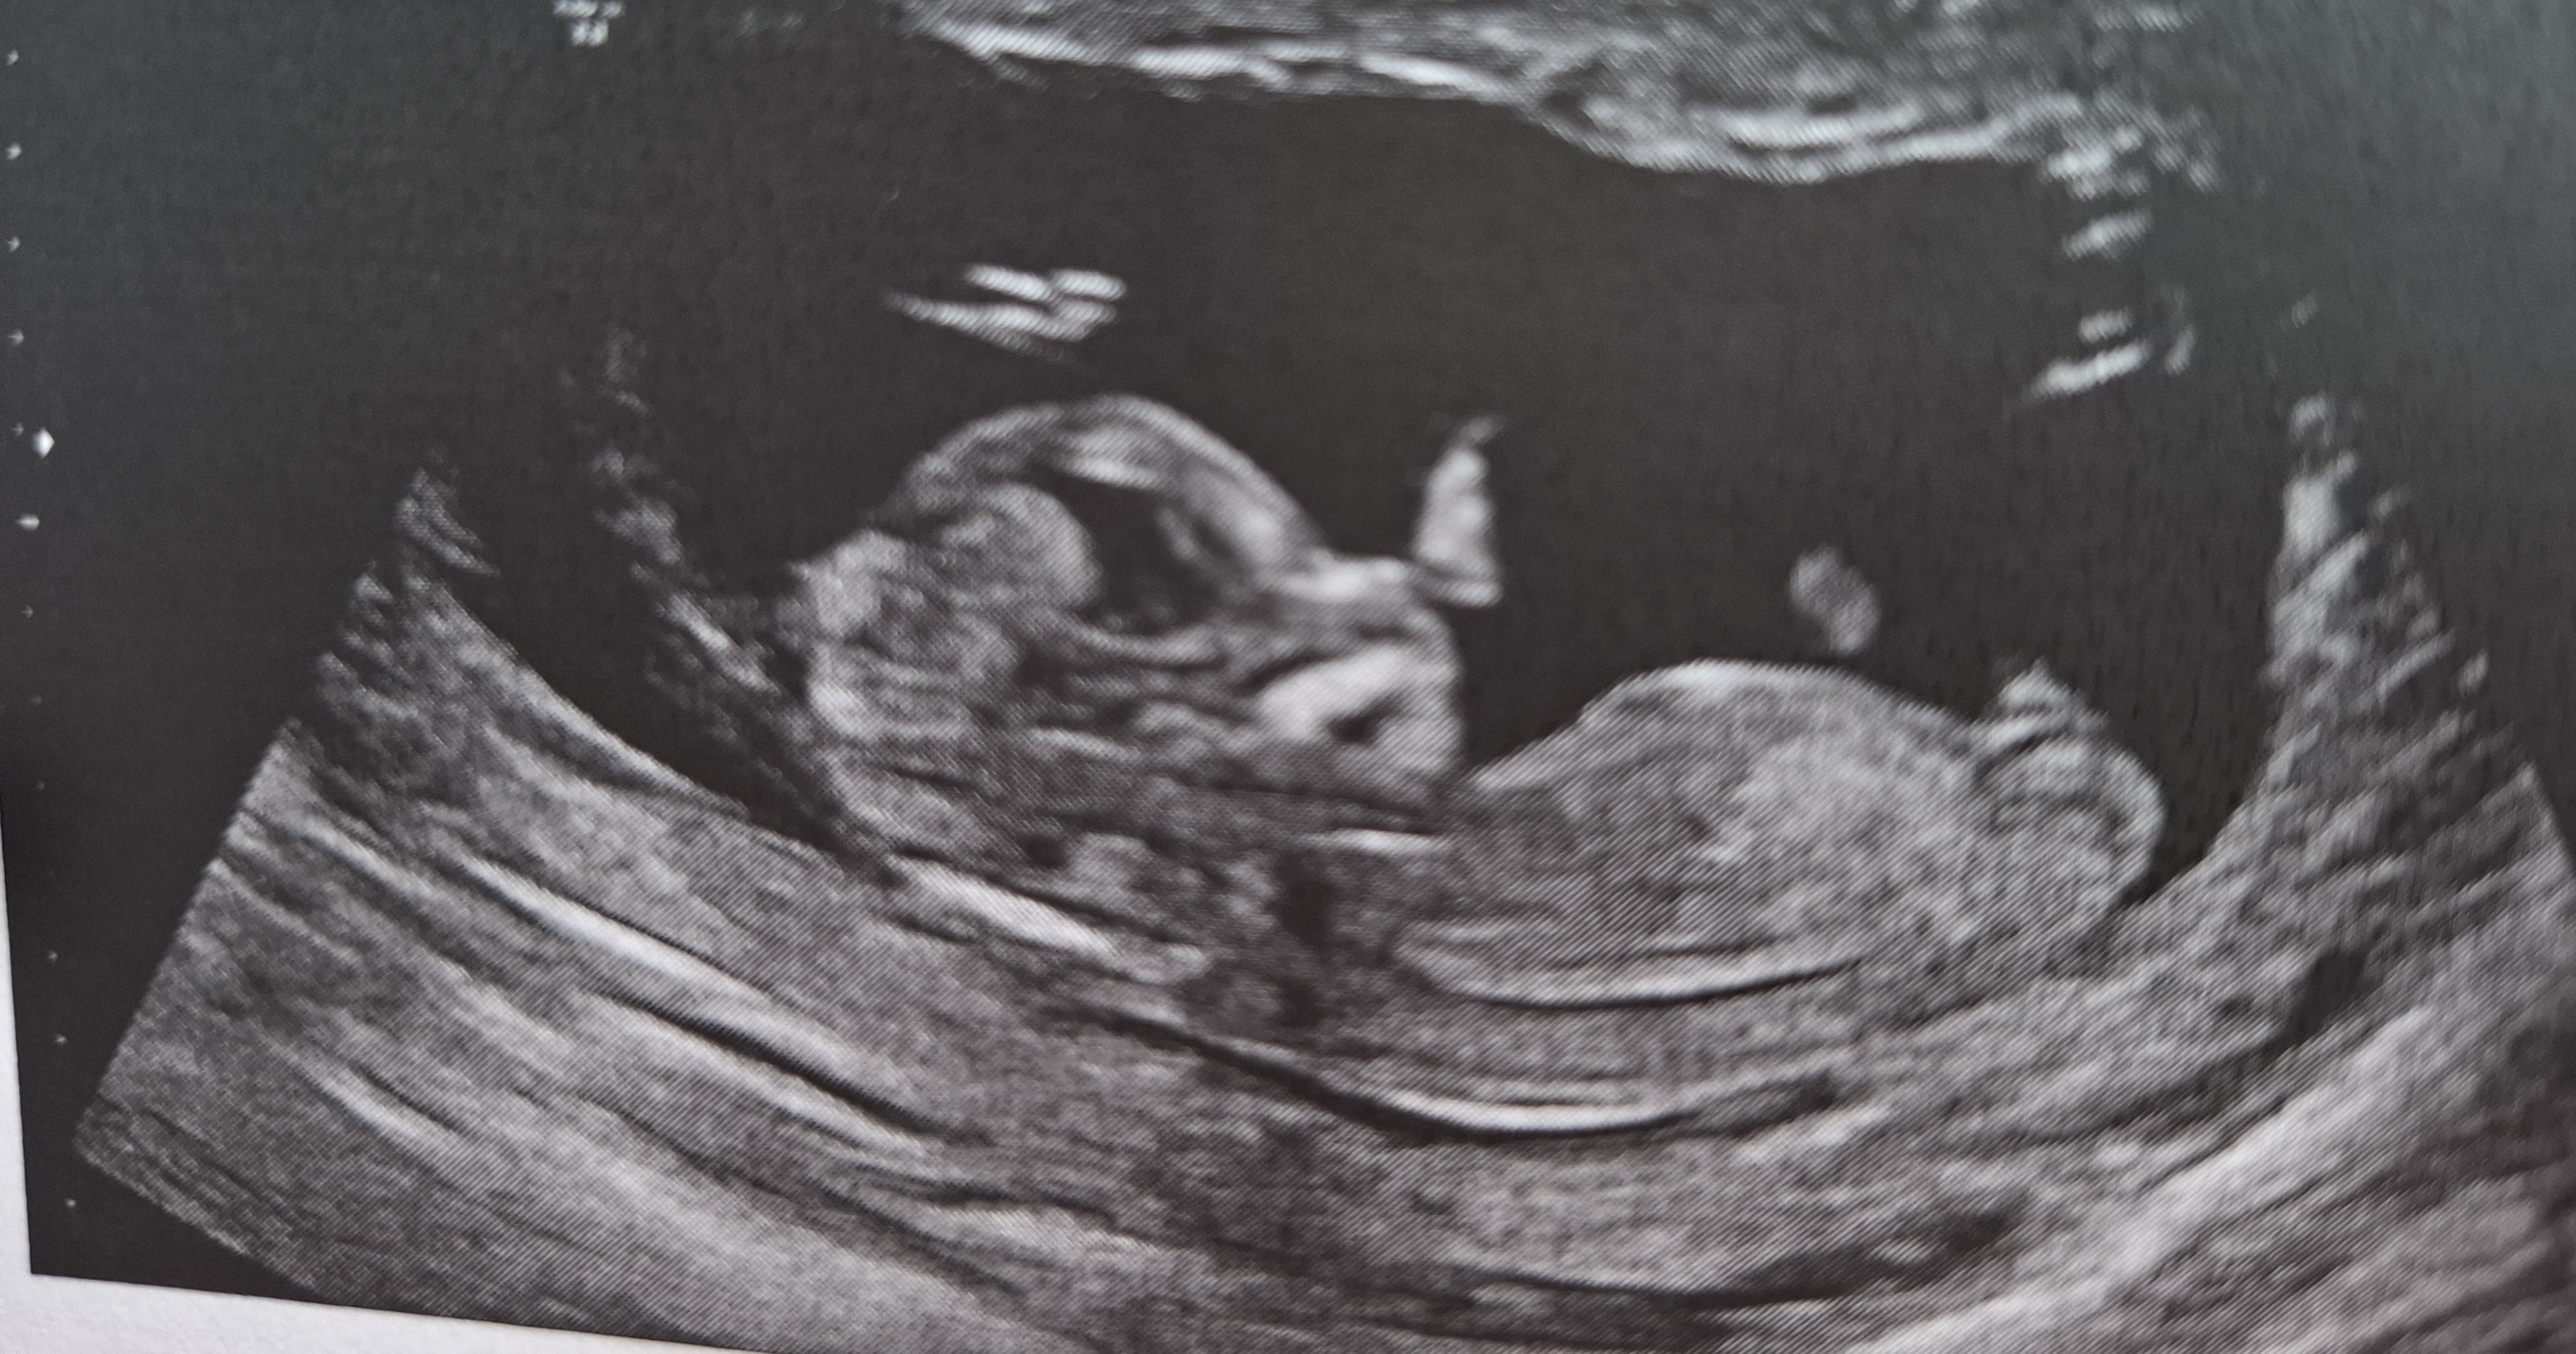

no ale jutro mam USG więc podejrzę tego mojego drugiego ancymonka.

Czy u Was lekarze w gabinetach mają usg z dodatkowym ekranem i widzicie wszystko na bierząco? U tego lekarza u którego będę jutro jest taki ekran co mnie bardzo cieszy, ale u tej drugiej lekarki nie ma i dopiero widzę dziecko na wydrukach z usg.